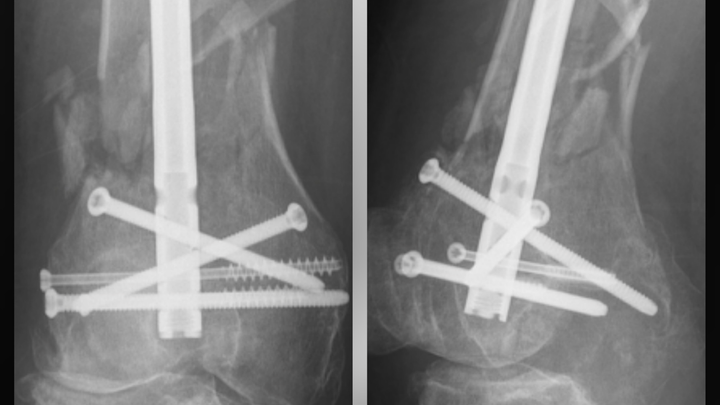

Hello friends.... the photo you see has 2 x-ray images of my right knee...as some of you know, I was involved in a very serious accident on January the 7th while riding my scooter. The result was a compound fracture of my right femur, shattered right kneecap and a torn ACL and further damage on the left leg. The other driver was 100% at faultI and EXTREMELY under insured. Eight hours of surgery, 12 days in the hospital....weeks later,I am STILL in a wheelchair and unable to walk...will not be able to work for at least the next two to three months, possibly longer....this is a LIFE ALTERING injury and I am struggling to afford rent, groceries, monthly bills, transportation to appointments and therapy. I am HUMBLY asking for your help by donating what you can and sharing as much as possible.